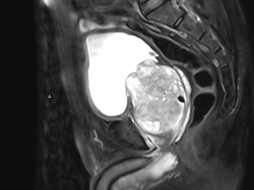

经检查,患者前列腺体积大小达到200ml,与蟠桃相当,而正常前列腺仅20ml,且合并巨大膀胱结石,这正是导致其症状加重的主要原因。